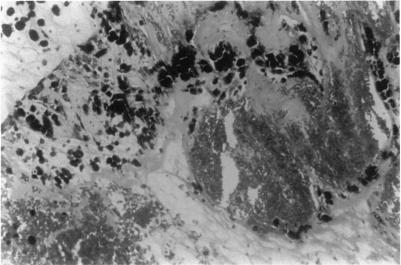

RESULTS

ANIMAL MODEL: Histopathologic examination of rabbit eyes treated with endocyclophotocoagulation demonstrated acute changes of ciliary process destruction, proteinaceous exudate, stromal edema, nuclear pyknosis, and pigment dispersion. Vascular congestion was seen with some hemorrhage. Later, replacement by fibrous or fibrovascular scar developed with loss of the pigmented and nonpigmented ciliary epithelia, absence of ciliary architectural elements, and pigment rounding and clumping. Human Eyes: Histopathologic examination of enucleated human eyes revealed total ablation of the ciliary processes with fibrosis and pigment clumping in areas of treatment. Abrupt transitions between treated and untreated regions could be identified. In some areas fibrocellular membrane proliferation was found extending over the scars that replaced the ciliary processes. Clinical series: Seventy-three patients were identified ranging in age from 2 to 85 years (mean, 57.7), with follow-up of 6 to 130 months (mean, 28.6). Mean number of previous operations was 3.5; mean number of previous glaucoma operations was 1.3. Preoperative mean IOP was 38 mmHg (range, 19 to 75), postoperative mean IOP was 16 mmHg (range, 1 to 50). At 6 months, 58 of 72 eyes (81%) with available IOP data had IOP greater than 5 mmHg and less than 22. At 12 months 48 of 55 (87.3%) were successfully controlled by these criteria, and at last follow-up 50 of 73 (68%). Fifty-six of 73 eyes (77%) were considered clinically stable at the last follow-up in terms of visual acuity, anatomic integrity, and IOP < or = 23 off all glaucoma medications. Visual acuity was stable or improved in 53 of 73 eyes (73%). Complications developed in 9 eyes (12%), including IOP < or = 6 mmHg in 6 eyes (8.2%), peripheral choroidal effusion in 4 (5.5%), fibrinous anterior chamber reaction in 3 (4.1%), phthisis in 2 (2.7%), and choroidal hemorrhage in 1. Thirty-five eyes had penetrating keratoplasty performed before or at the same time as endolaser (an average of 2.14 grafts each), Graft rejection occurred in 4 eyes (11%), and long-term failure of grafts occurred in 11 of 35 (31%). In 31 eyes, additional surgical procedures were performed at the time of endocyclophotocoagulation.

动物模型:经睫状体光凝术治疗的兔眼组织病理学检查显示睫状体破坏、蛋白质渗出、基质水肿、核固缩和色素弥散的急性变化。可见血管充血伴一些出血。之后,出现纤维或纤维血管瘢痕替代,色素性和非色素性睫状体上皮消失,睫状体结构成分缺失,色素聚集。人眼:摘除的人眼组织病理学检查显示睫状体完全消融,治疗区域有纤维化和色素聚集。可识别出治疗区域与未治疗区域之间的突然转变。在一些区域发现纤维细胞膜增生延伸至替代睫状体的瘢痕上。临床系列:共识别出73例患者,年龄2至85岁(平均57.7岁),随访6至130个月(平均28.6个月)。既往手术平均次数为3.5次;既往青光眼手术平均次数为1.3次。术前平均眼压为38 mmHg(范围19至75 mmHg),术后平均眼压为16 mmHg(范围1至50 mmHg)。在6个月时,72只可获得眼压数据的眼中,58只(81%)眼压高于5 mmHg且低于22 mmHg。在12个月时,55只眼中的48只(87.3%)按此标准眼压得到成功控制,在最后一次随访时,73只眼中的50只(68%)眼压得到控制。在最后一次随访时,73只眼中的56只(77%)在视力、解剖结构完整性及停用所有青光眼药物后眼压≤23 mmHg方面被认为临床稳定。73只眼中的53只(73%)视力稳定或提高。9只眼(12%)出现并发症,包括6只眼(8.2%)眼压≤6 mmHg,4只眼(5.5%)周边脉络膜积液,3只眼(4.1%)纤维素性前房反应,2只眼(2.7%)眼球痨,1只眼脉络膜出血。35只眼在激光睫状体光凝术前或同时进行了穿透性角膜移植术(平均每只眼2.14次移植),4只眼(11%)发生移植排斥,35只眼中11只(31%)移植长期失败。31只眼在激光睫状体光凝术时进行了额外的手术操作。